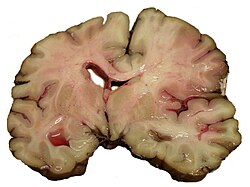

Intracerebralno krvarenje

Obično se javlja u malim arterijama ili arteriolama i najčešće nastaje zbog povišenog krvnog tlaka[24], vaskularnih malformacija središnjeg živčanog sustava (uključujući kavernozne angiome ili arterijskovenske malformacije), cerebralne amiloidne angiopatije ili infarkta u kojima se sekundarno razvilo krvarenje[2]. Drugi potencijalni uzroci su trauma, poremećaji koagulacije, amiloidne angiopatije, komzumiranje droge (npr. amfetamini ili kokain). Hematom se povećava sve dok pritisak okolnog tkiva ne ograniči njegov rast ili ne dođe do dekompresije pražnjenjem u cerebralni ventrikularni sustav, cerebrospinalnu tekućinu ili pialnu površinu. Trećina intrecerebralnog krvarenja je krvarenje u moždane komore. Intracerebralno krvarenje ima smrtnost od 44% nakon 30 dana, višu od ishemijskog moždang udara ili subarahnoidalnog krvarenja (koji e tehnički mogu klasificirati kao vrsta moždanog udara)[2].